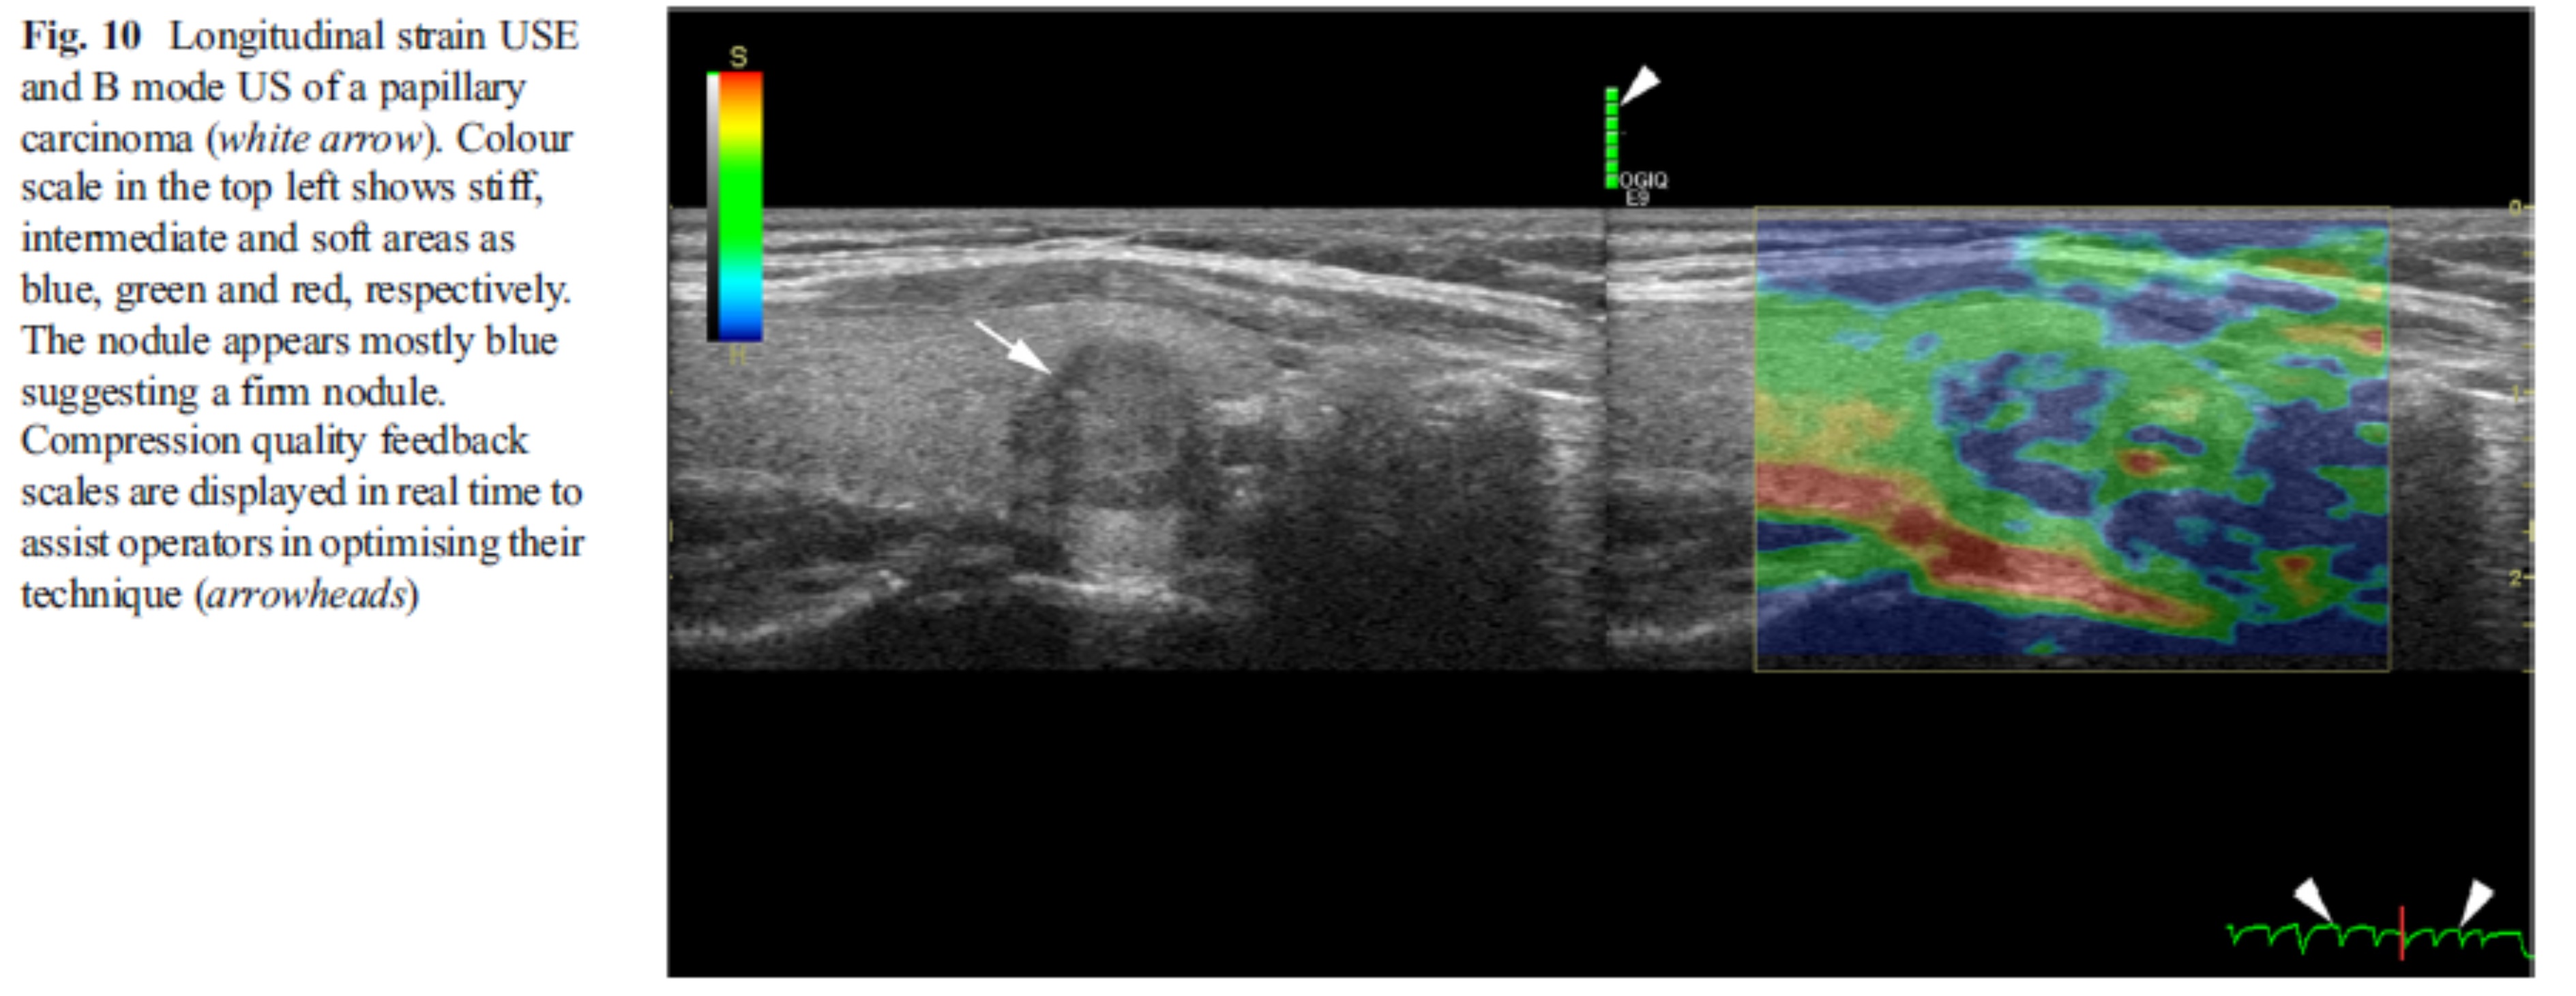

가운데에 보이는 악성 결절이 단단하게 (파랗게)보인다.